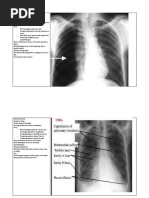

FOTO THORAX NORMAL ( orang dewasa )

Cor tidak membesar, sinuses dan diafragma normal

Pulmo : Hili normal

Corakan paru bertambah

Tidak tampak perbercakan lunak

Kesan : Tidak tampak TB paru aktif

Tidak tampak pembesaran jantung

FOTO THORAX NORMAL ( pada anak )

Kesan : Tidak tampak spesifik proses aktif